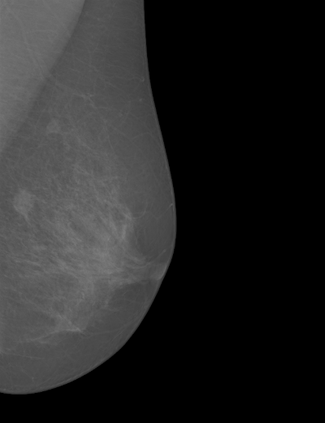

Breast cancer is the most widespread neoplasm among women and early detection of this disease is critical. Deep learning techniques have become of great interest to improve diagnostic performance. Nonetheless, discriminating between malignant and benign masses from whole mammograms remains challenging due to them being almost identical to an untrained eye and the region of interest (ROI) occupying a minuscule portion of the entire image. In this paper, we propose a framework, parameterized hypercomplex attention maps (PHAM), to overcome these problems. Specifically, we deploy an augmentation step based on computing attention maps. Then, the attention maps are used to condition the classification step by constructing a multi-dimensional input comprised of the original breast cancer image and the corresponding attention map. In this step, a parameterized hypercomplex neural network (PHNN) is employed to perform breast cancer classification. The framework offers two main advantages. First, attention maps provide critical information regarding the ROI and allow the neural model to concentrate on it. Second, the hypercomplex architecture has the ability to model local relations between input dimensions thanks to hypercomplex algebra rules, thus properly exploiting the information provided by the attention map. We demonstrate the efficacy of the proposed framework on both mammography images as well as histopathological ones, surpassing attention-based state-of-the-art networks and the real-valued counterpart of our method. The code of our work is available at https://github.com/elelo22/AttentionBCS.